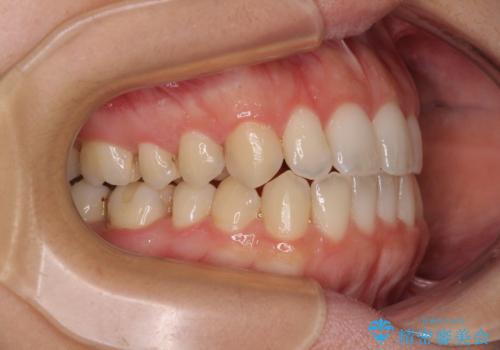

【モニター】オープンバイトをインビザライン矯正で治す

- 前歯の開咬を気にして来院された患者様です。

開咬の治療は、前歯を閉じるように動かすとともに、上下臼歯を圧下(骨内にめり込ませる)させることで進めて行きます。

インビザラインは臼歯の圧下を効果的に行えるため、インビザラインを用いて矯正治療を行うこととしました。